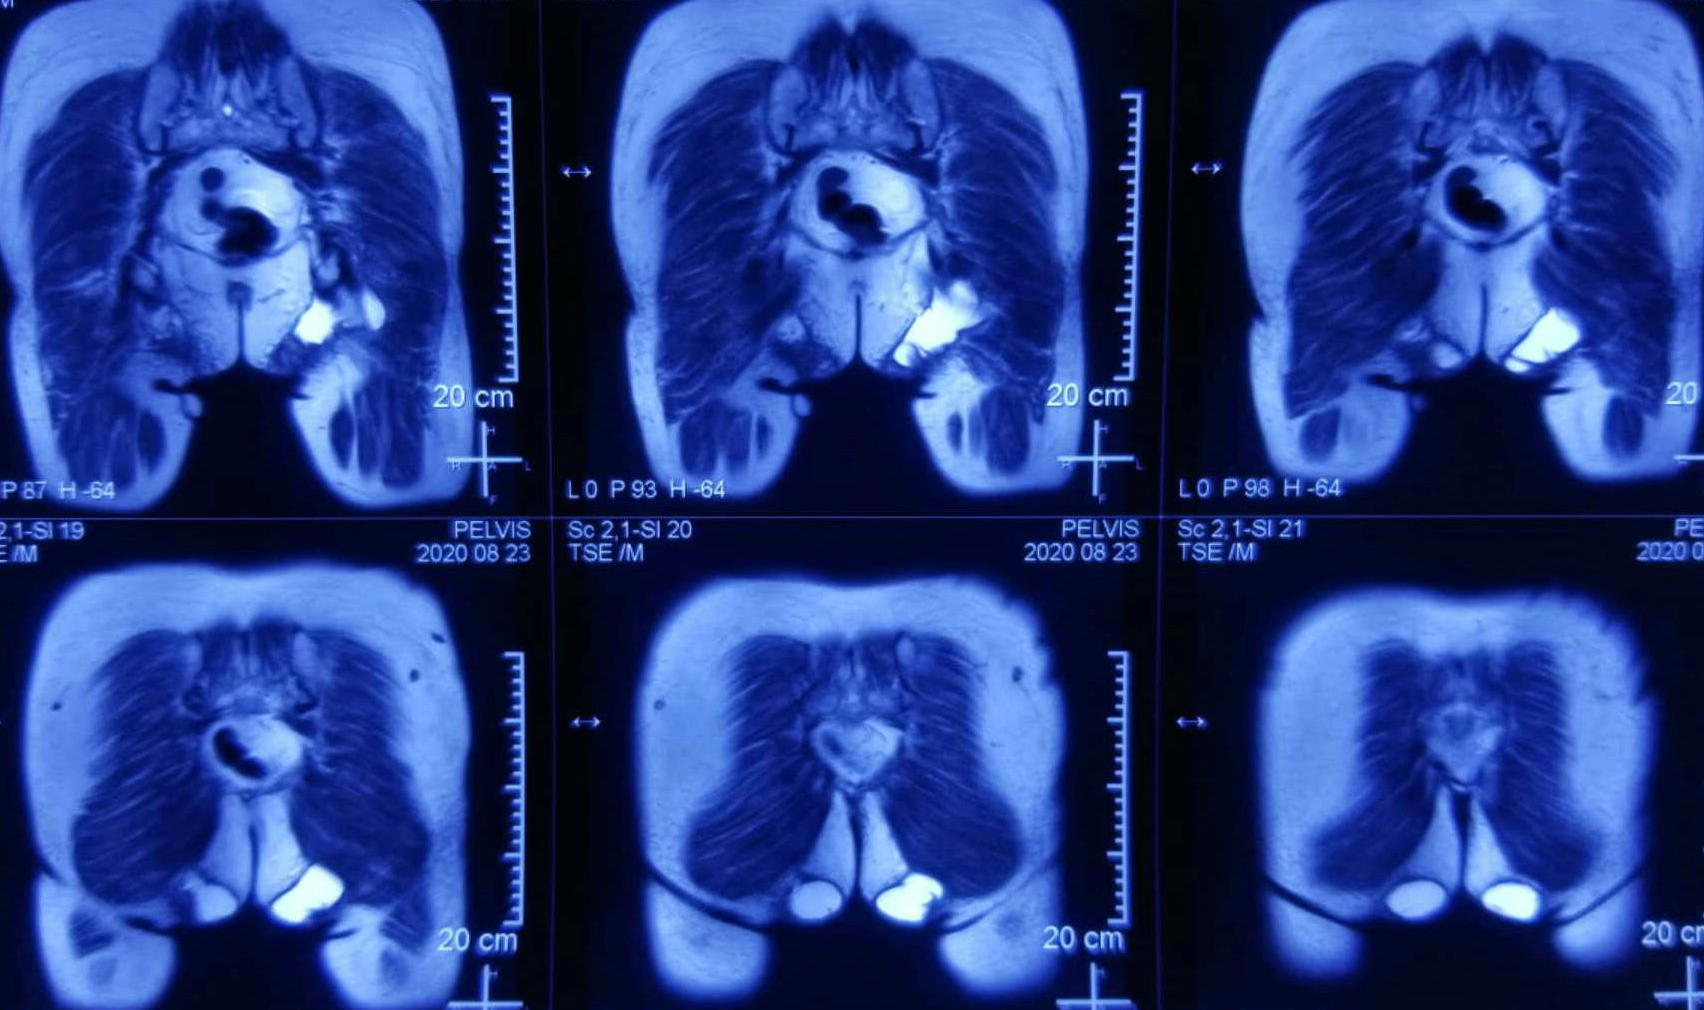

双髋冠状面MRI

患者,女性,72岁,因进行性臀部包块增大伴坐位不适4月以恶性臀部肿瘤入院。近4月以来,发现双侧臀部包块,从鸡蛋大发展至较大肿块,伴坐位不适感和大便时不适感。患者有近30年类风湿性关节炎既往病史,近8年以来双膝疼痛加重、跛行并伴有严重内翻畸形,行走非常困难,主要以双手撑地,臀部着地方式移动身体,即“以臀代步”,日常生活以坐姿为主。入院后,我院继续完善相关检查,超声提示患者左、右臀部皮下分别探及约4.7×3.6,3.6×3.2cm大小的无回声包块,外形不规则,下缘向软组织深部延伸,边界尚清,内透声欠佳,其内可见细密点状漂浮,诊断意见为双侧臀部皮下囊性占位病变,经核磁及CT进一步诊断为囊性占位病变深及坐骨结节及肛门肌群旁,穿刺活检提示符合良性囊性病变。术前,确诊为双侧臀部皮下及深部巨大囊肿。